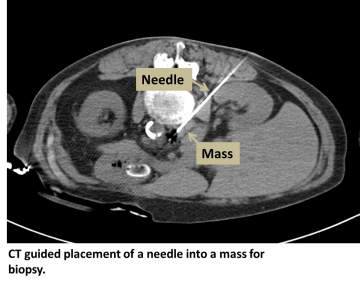

An interventional radiologist uses CT or ultrasound to pass an introducer needle into the tissue of interest. Once position is confirmed, a biopsy needle is passed through the introducer needle and used to take samples until adequate tissue is obtained.